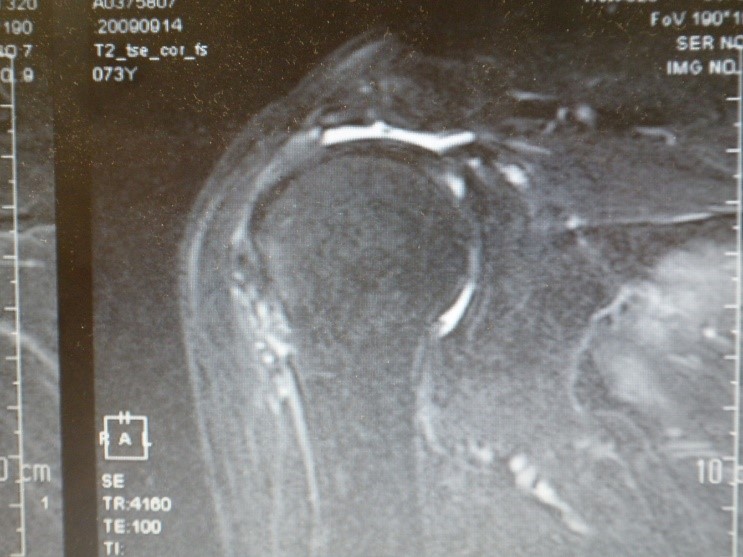

診断は、病歴、触診、可動域制限の有無、超音波検査、X線検査、MRI検査で行います。(図1、2)

ここで注意していただきたいのは、MRI検査放射線科読影の腱板損傷と腱板断裂の表記の違いです。腱板周囲に炎症所見があれば損傷、明らかに腱が切れているものを断裂と表記されることが多いのです。すなわち、損傷は拘縮、石灰沈着症、部分断裂でも損傷となります。患者さんで40代の時に腱板痛めたが自然に治ったとお話しされる方がいらっしゃりますが、おそらく断裂でなく損傷だったのでしょう。